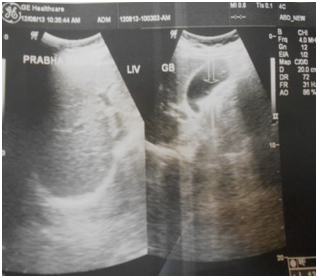

Conclusively, patients of asymptomatic and uncomplicated biliary sludge must be given chance to recover from their ailment by offering them “Srivastava regimen for biliary sludge” which contains oral ampicillin, UDCA and Phaltrikadi Kvatha (decoction) or Ghanbati (Tablet) for minimum of 45days, dietary fat restriction, plenty of water intake and avoiding all the possible confounding factors of gallstone diseases. In most of the patients, biliary sludge vanishes and gallbladder appears completely normal in ultrasonography (Figure 1) (Figure 2). Laparoscopic cholecystectomy remains gold standard treatment for complicated biliary sludge. In our opinion, one should try to avoid cholecystectomy in asymptomatic and even mild symptomatic cases as most of the patients give acceptable response to conservative management. By this we can not only avoid unnecessary expensive surgical burden to healthcare system but also save stress of our patients and not least poor gallbladder. We also want researchers to ponder further conclusive research trials which enable us better understanding of the pathogenesis of biliary sludge and further elucidation of the mechanism of action of these ayurvedic preparations at the molecular level for scientific basis of treatment. We have designed our regimen on the basis of available scientific researches and traditional ayurvedic literature and found that integrated approach of medicine works wonderfully and it is need of time.

Figure 1 Pre-treatment ultrasonography scan showing biliary sludge.